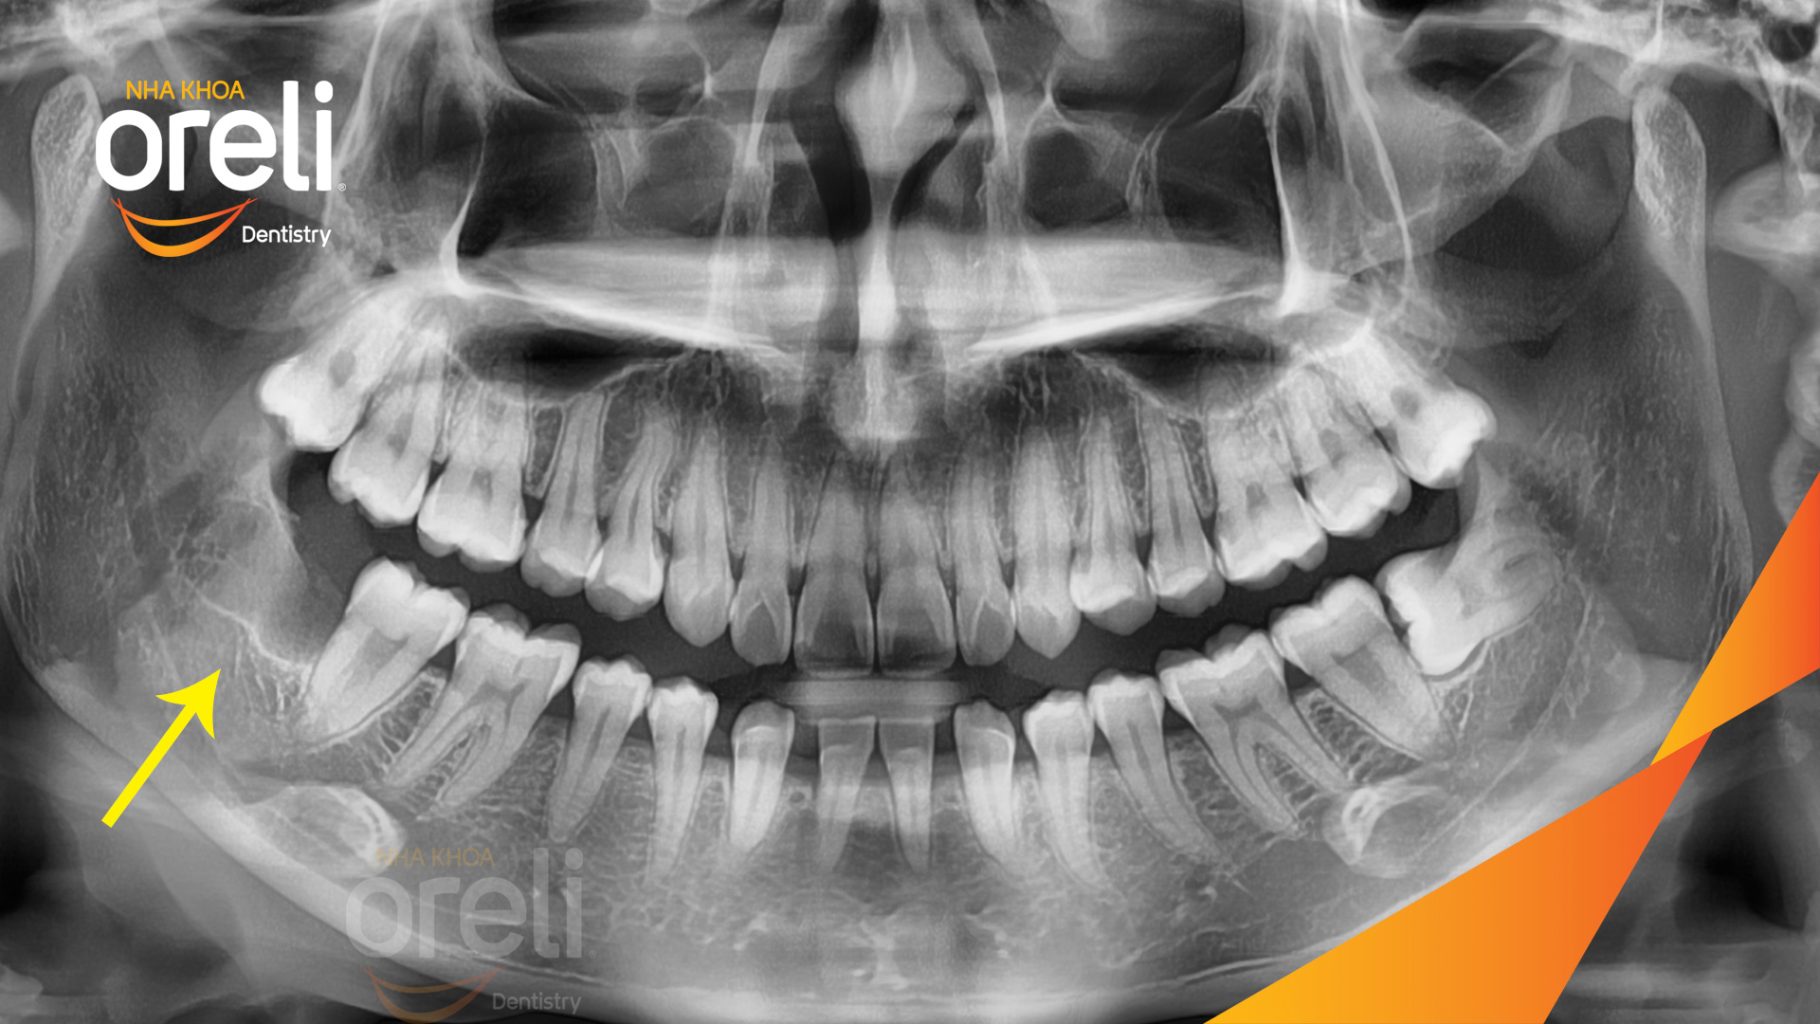

Nhổ răng khôn hàm dưới mọc lệch – Ca thực tế tại Oreli Buôn Ma Thuột

Tình trạng: Răng khôn hàm dưới mọc lệch ngang 90 độ

Giải pháp: Nhổ răng khôn hàm dưới bên trái

Kết quả: Toàn bộ răng 8 hàm dưới bên trái được lấy bỏ

Hình ảnh thực tế